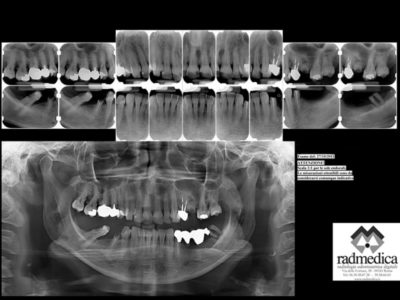

Grazie alla completa informatizzazione dello studio, è possibile comunicare con il proprio medico in formato elettronico. Con l’invio di documentazione varia, rapporti medici, radiografie e fotografie attraverso posta elettronica, per richiedere un’opinione medica e la valutazione approssimativa delle spese dei trattamenti necessari, vengono resi possibili anche senza un incontro diretto con il medico.